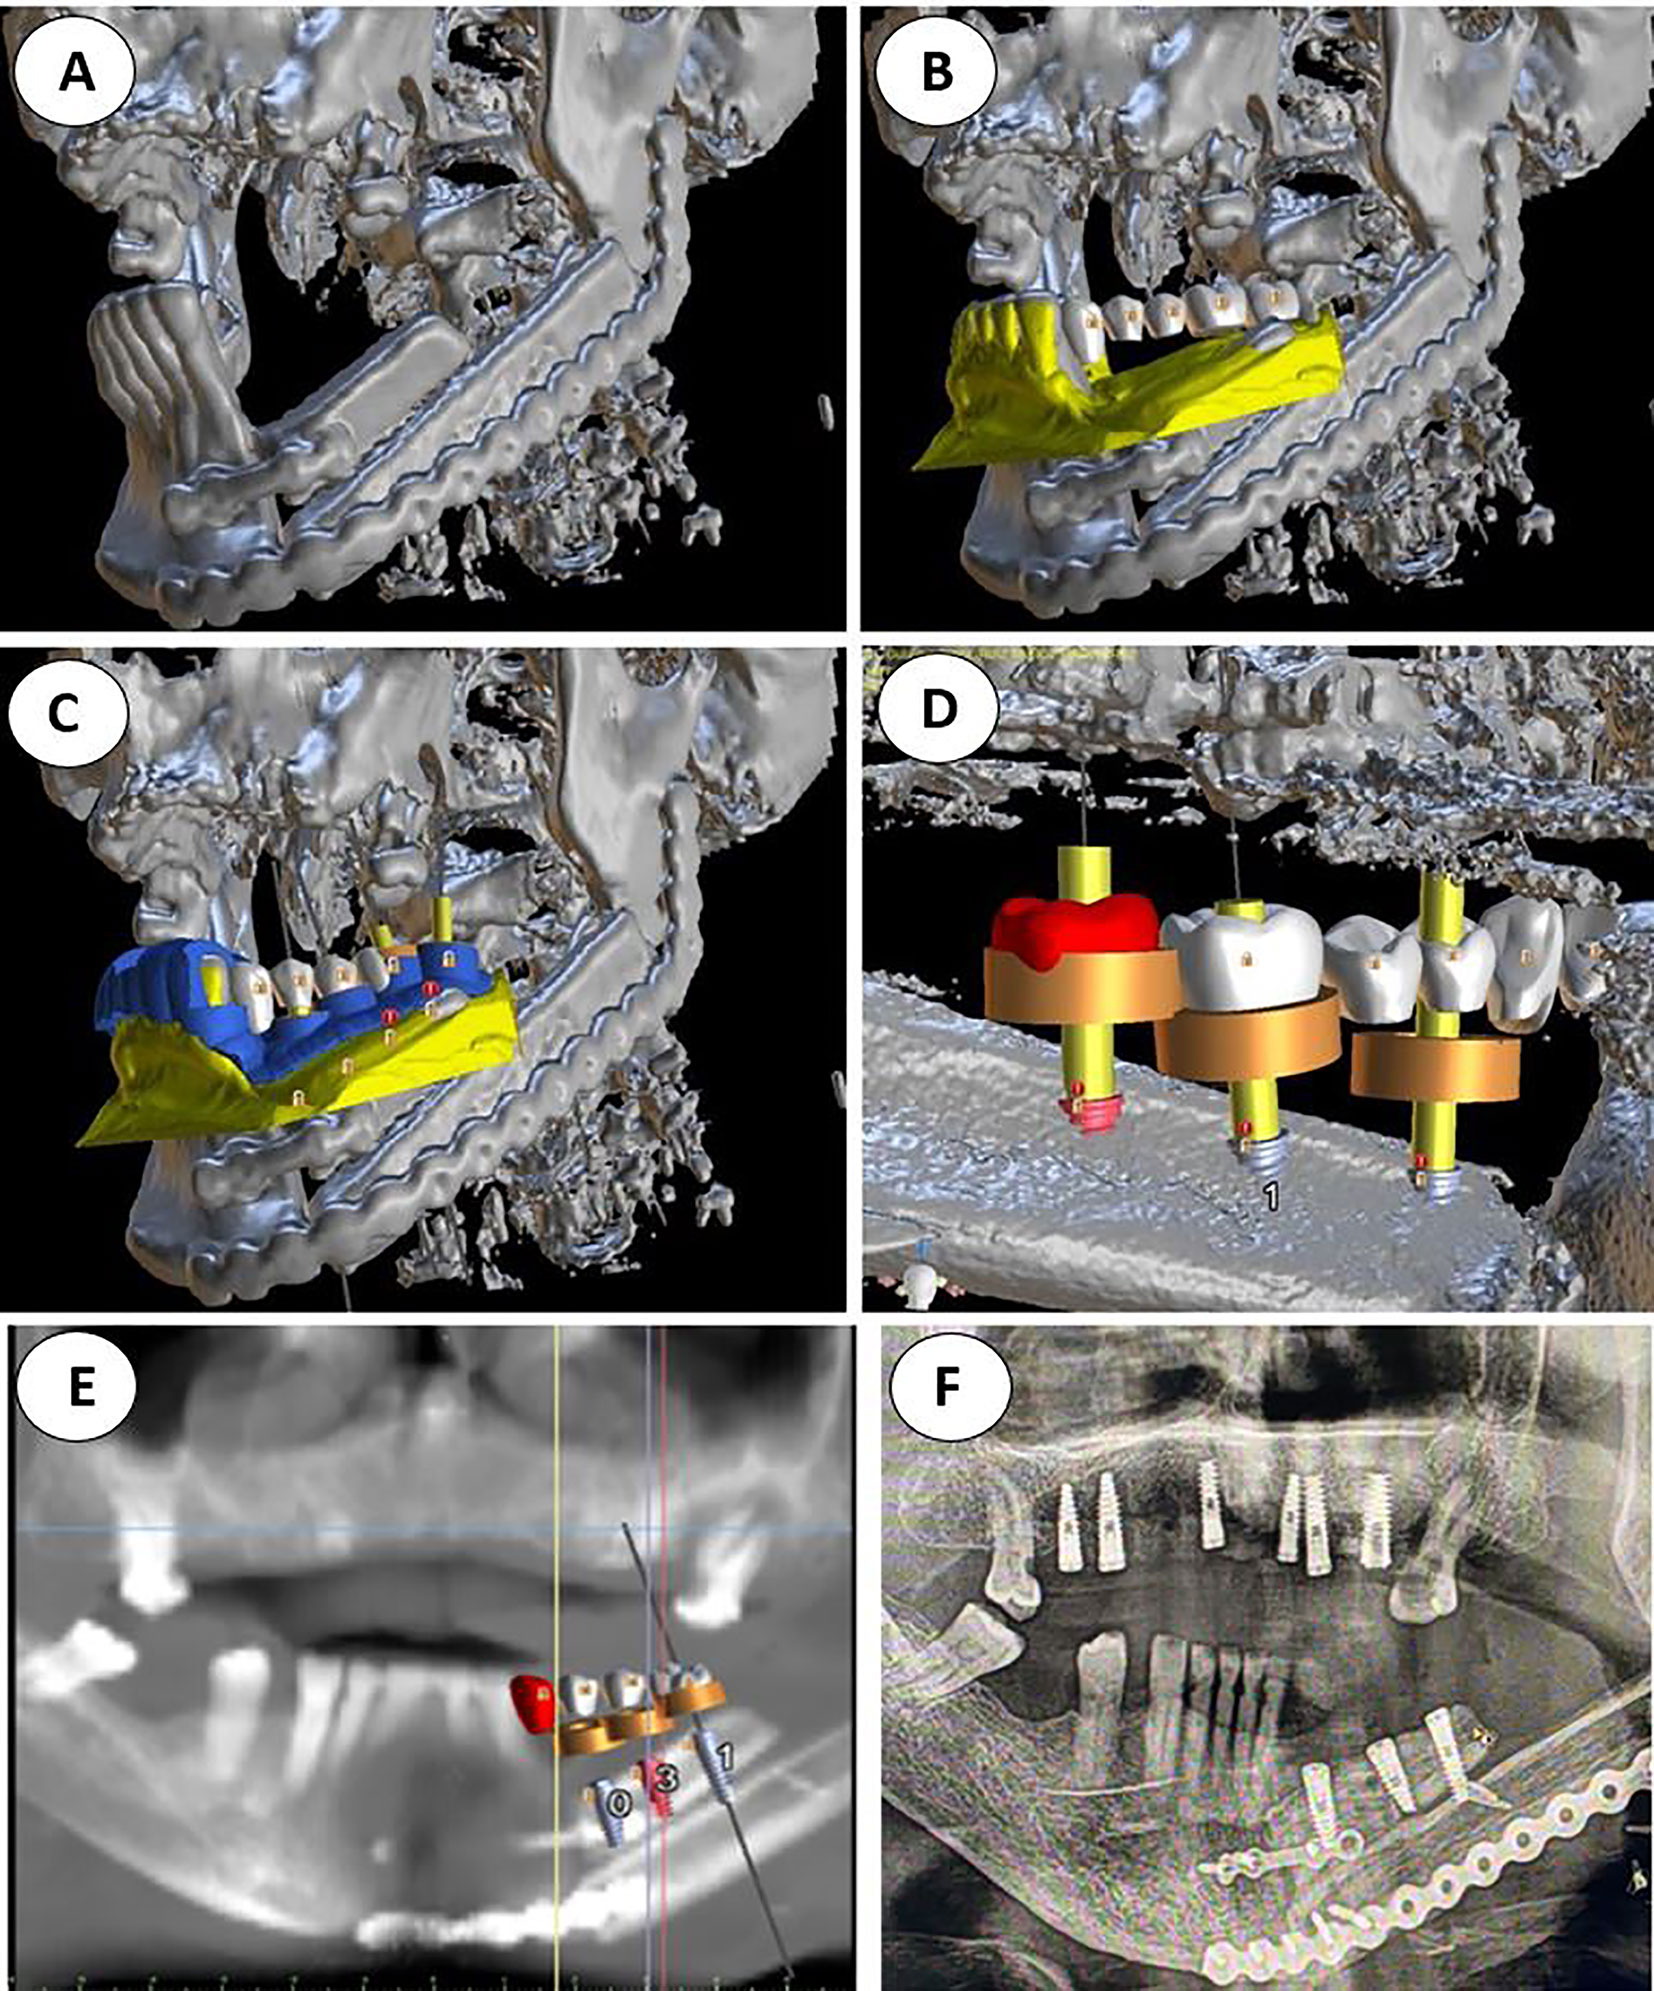

Calibration In Dynamic Navigation Surgery In Implamt

Browse our specialized Calibration In Dynamic Navigation Surgery In Implamt portfolio with numerous expertly curated photographs. optimized for both digital and print applications across multiple platforms. providing reliable visual resources for business and academic use. Each Calibration In Dynamic Navigation Surgery In Implamt image is carefully selected for superior visual impact and professional quality. Perfect for marketing materials, corporate presentations, advertising campaigns, and professional publications All Calibration In Dynamic Navigation Surgery In Implamt images are available in high resolution with professional-grade quality, optimized for both digital and print applications, and include comprehensive metadata for easy organization and usage. Our Calibration In Dynamic Navigation Surgery In Implamt collection provides reliable visual resources for business presentations and marketing materials. Whether for commercial projects or personal use, our Calibration In Dynamic Navigation Surgery In Implamt collection delivers consistent excellence. The Calibration In Dynamic Navigation Surgery In Implamt archive serves professionals, educators, and creatives across diverse industries. Regular updates keep the Calibration In Dynamic Navigation Surgery In Implamt collection current with contemporary trends and styles. Advanced search capabilities make finding the perfect Calibration In Dynamic Navigation Surgery In Implamt image effortless and efficient. Multiple resolution options ensure optimal performance across different platforms and applications.